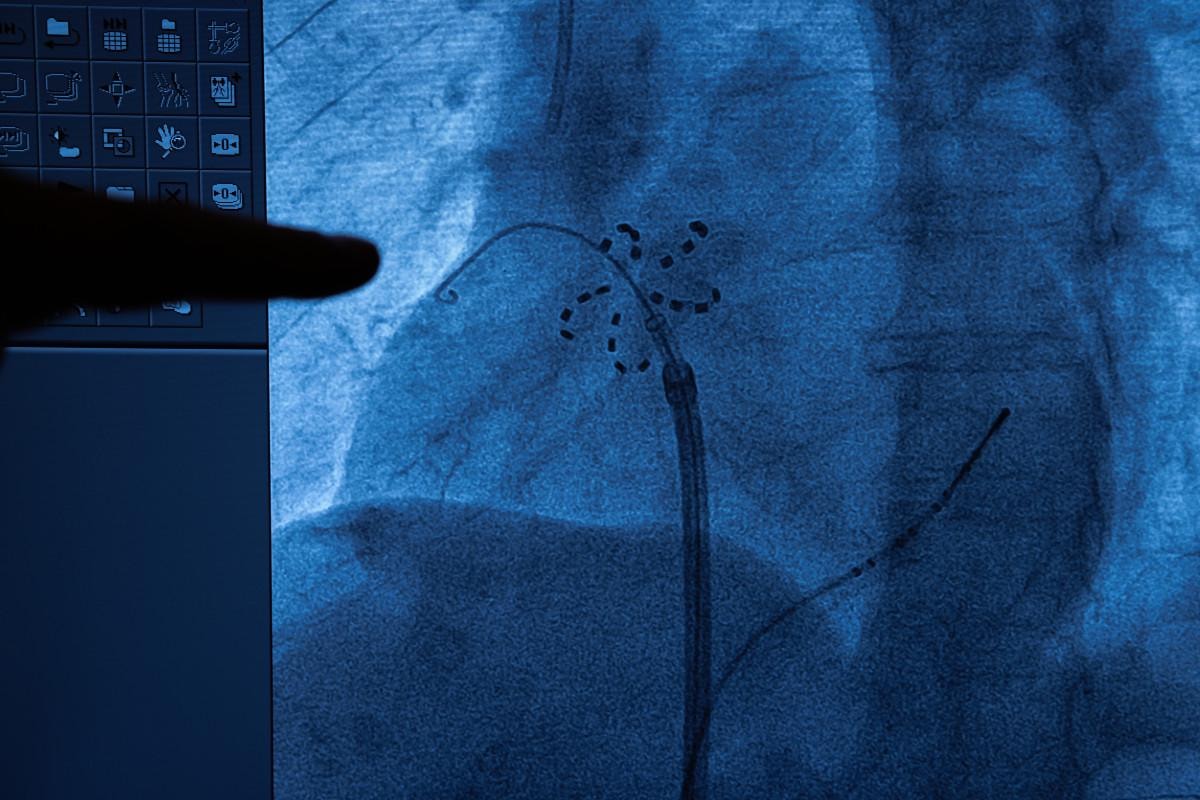

PFA ile bu önemli risklerin hiçbiri görülmüyor. PFA yöntemi, kasıktan damar yoluyla ilerletilen kateterle uygulanıyor.

Kateter ucundaki elektrot, problemli dokulara yüksek frekanslı elektrik dalgası gönderiyor ve bu dokuların elektriksel aktivasyonu ortadan kalkıyor. Böylece ritim bozukluğu tedavi edilmiş oluyor” dedi.